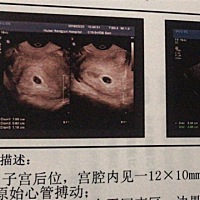

能看出来是男宝 还是女宝吗